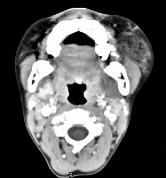

问题 男,12岁,左面颊肿大5年余,局部呈紫红色,CT如图所示,最可能诊断为()

选项 A.蔓状血管瘤 B.血管外皮瘤 C.动静脉畸形 D.慢性腮腺炎 E.下颌下腺慢性炎症

答案 A